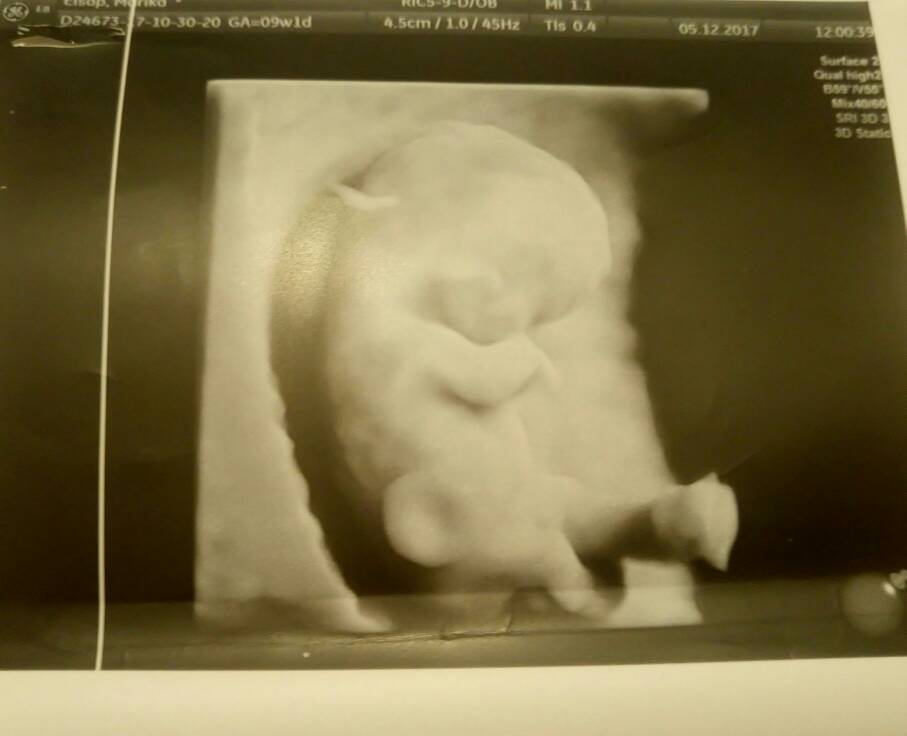

Hej dziewczyny ;) przedstawiam wam moją już nie fasolkę :) z OM 9+1 z USG 9+5 :) i póki co wszystko dobrze :)

1512481217-26c39ed7751d30dc-aaaaaa.jpeg

Prawie 3mc szczęścia :)